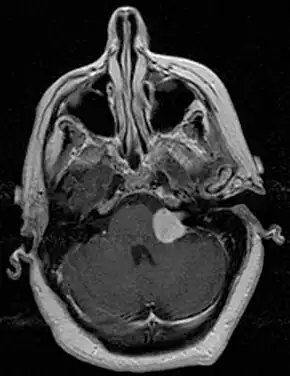

![]() | |

| Bilateral schwannomas in a person with neurofibromatosis 2 | |